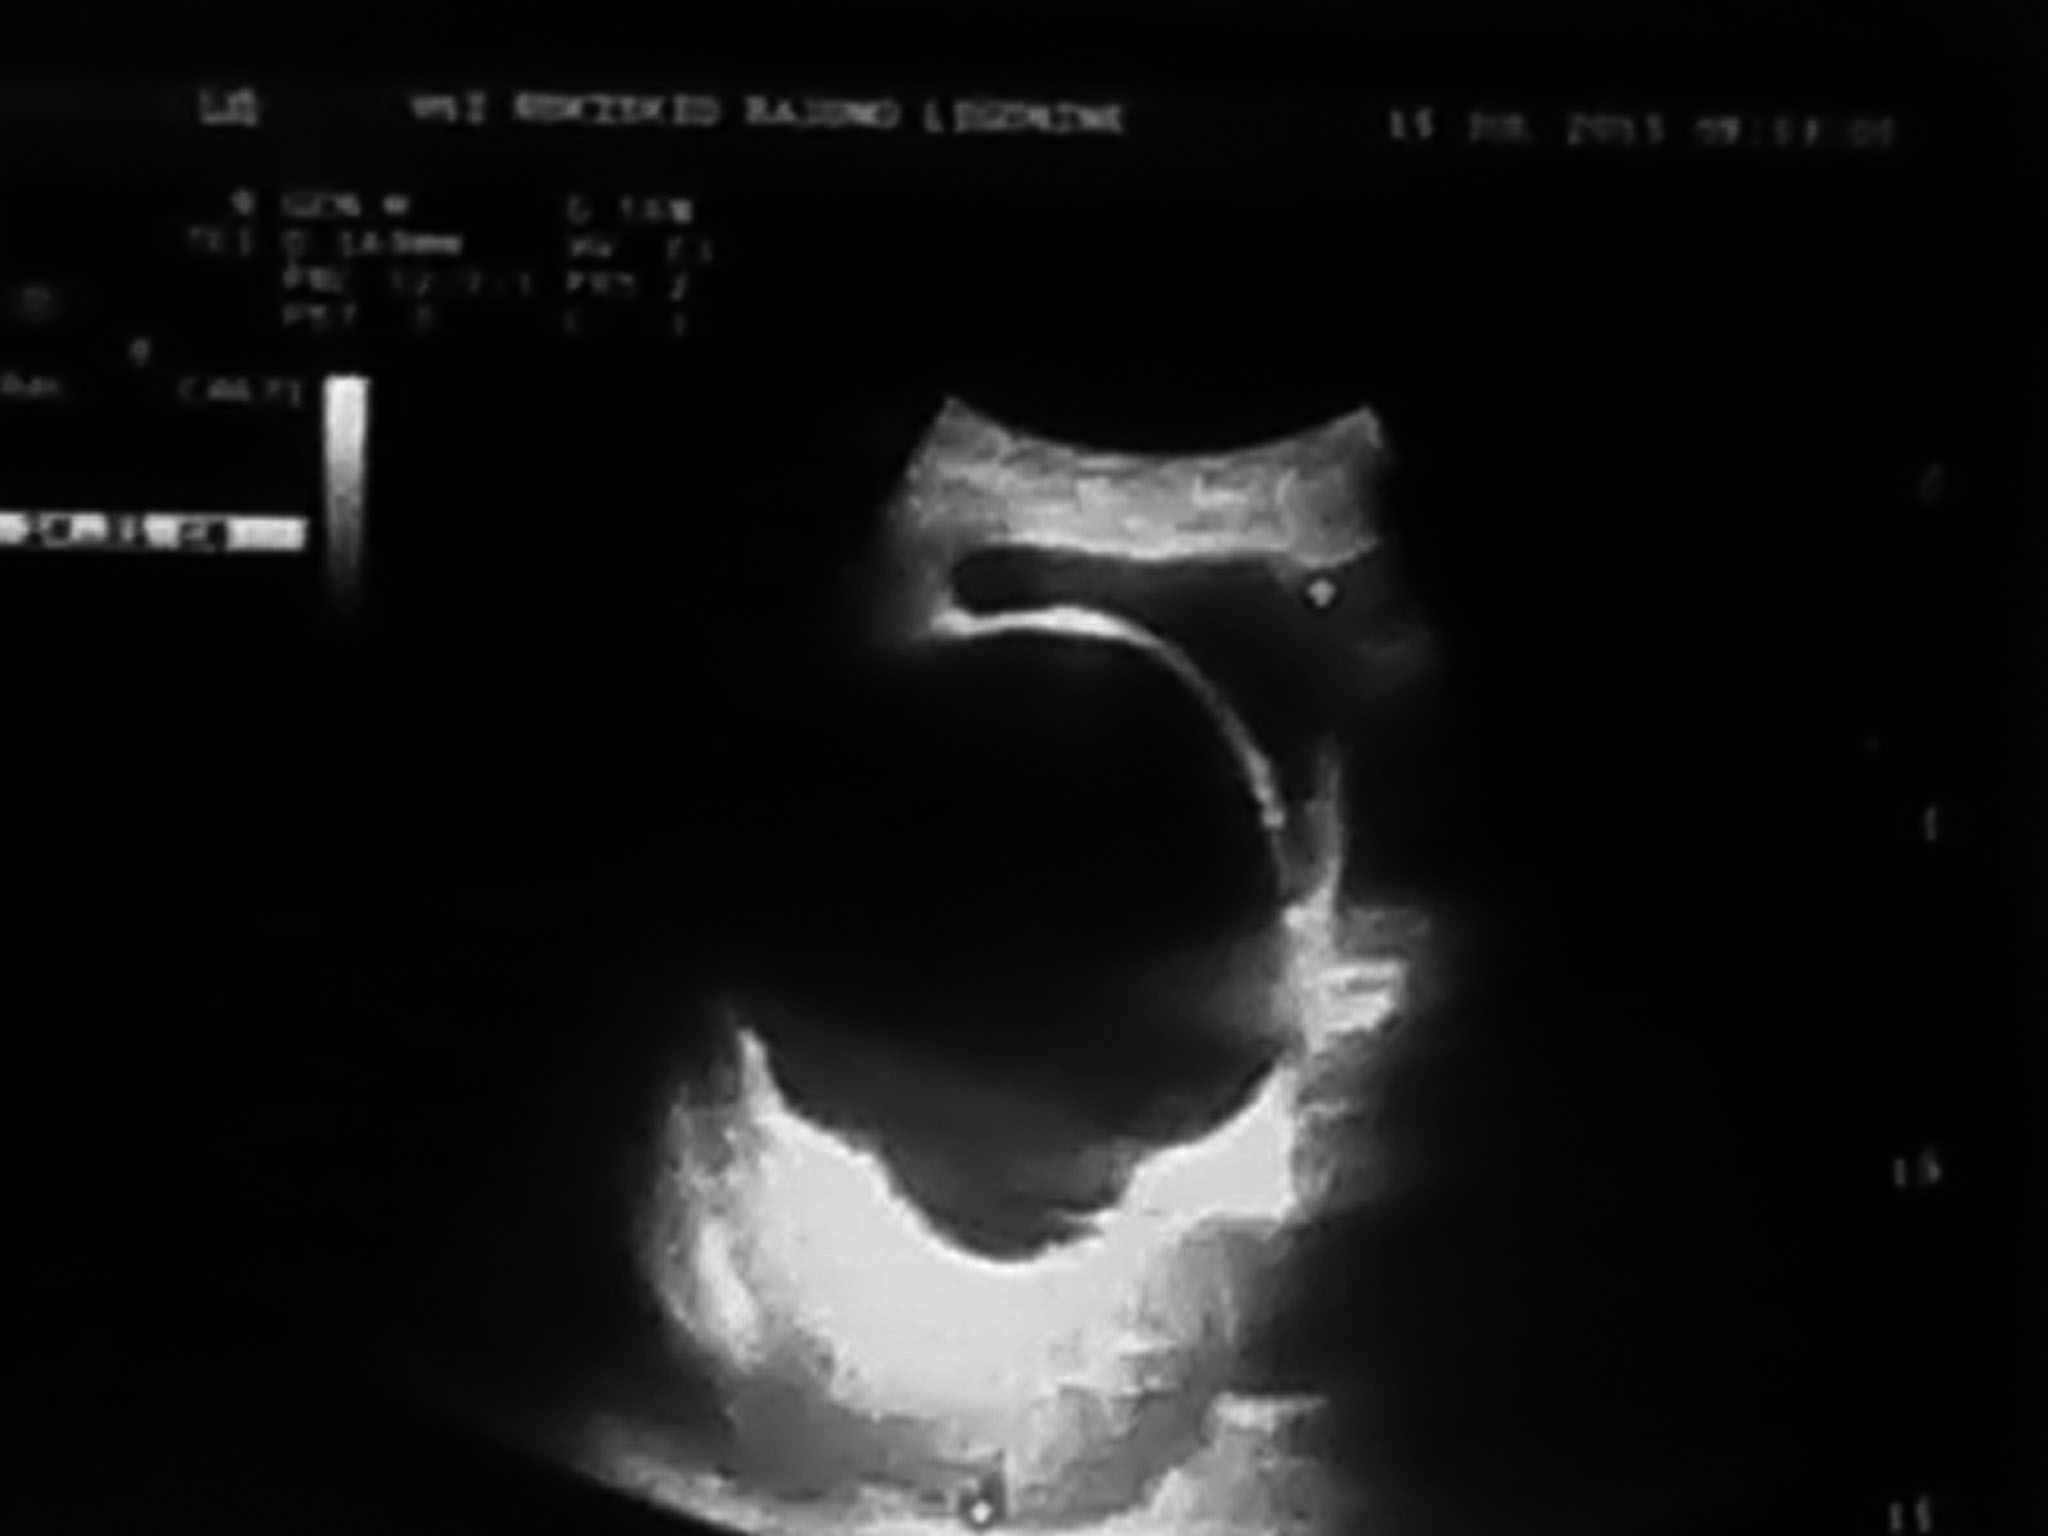

Снимок, конечно, безобразный и плохочитаемый.

Похоже на кисту печени больших размеров.